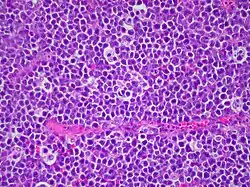

Das Burkitt-Lymphom (BL, englisch Burkitt’s lymphoma) ist ein malignes Lymphom und wird zu den B-Zell-Non-Hodgkin-Lymphomen gezählt. Es ist nach seinem Erstbeschreiber, dem britischen Chirurgen Denis Parsons Burkitt benannt.[1]

Das BL ist einer der am schnellsten wachsenden humanen Tumoren und hat entsprechend eine außerordentlich hohe Zellteilungsrate (der sogenannte Ki-67-Index ist größer 95 %, d. h. mehr als 95 % der Zellen befinden sich in Teilung). Gerade wegen des rasanten Wachstums ist der Tumor jedoch in der Regel sehr empfindlich gegenüber Chemotherapie und Strahlentherapie. Bei ausgeprägtem Knochenmarkbefall durch das BL (>20 % Zellanteil) spricht man auch von Burkitt-Leukämie oder „reifzelliger B-ALL“/„L3-ALL“. Dies ist ein seltenes Krankheitsbild (nur ca. 3–5 % aller akuten lymphatischen Leukämien, d. h. in ganz Deutschland weniger als 100 Fälle pro Jahr).